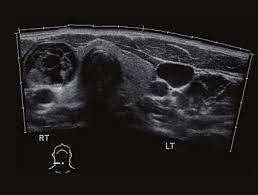

Toshiba Xario™ XG je barevný ultrazvukový systém se sdílenými službami Doppler, který kombinuje vynikající kvalitu obrazu s ergonomickým designem. Tento všestranný přístroj je vybaven řadou pokročilých funkcí, které zajišťují konzistentní poskytování vysoce kvalitních snímků v širokém spektru klinických aplikací, včetně břicha, prsou, malých částí, štítné žlázy a specializovaných OB/GYN aplikací s 3D/4D zobrazením.

- Všestranné použití: Aplikace pro břicho, prsa, malé části, štítnou žlázu a OB/GYN.

- Vynikající kvalita obrazu: Detailní a jasné zobrazení pro přesnou diagnostiku.

- ApliPure™: Technologie pro vynikající čistotu a detaily obrazu ve všech režimech.